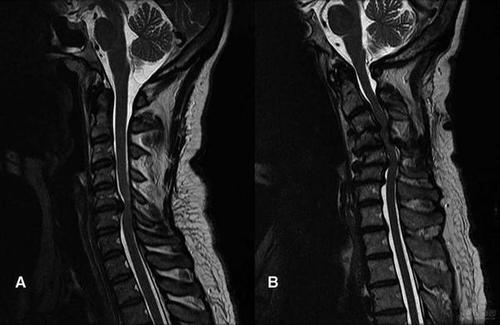

2.脊髓型颈椎病:由于颈椎退变结构压迫脊髓或压迫供应脊髓的血管而出现一系列症状,包括四肢感觉、运动、反射以及二便功能障碍的综合征,为颈椎病最严重的类型。由于下颈段椎管相对较小且活动度大,故退变亦发生较早、较重,脊髓受压也易发生在下颈段病人出现上肢或下肢麻木无力、僵硬、双足踩棉花感,束带感,双手无法做精细动作,如穿针,有些门诊患者就说“自己不能下楼梯和走下坡路,容易摔倒,感觉自己腿不停使唤,刹不住车的感觉”。后期可出现大小便功能障碍。